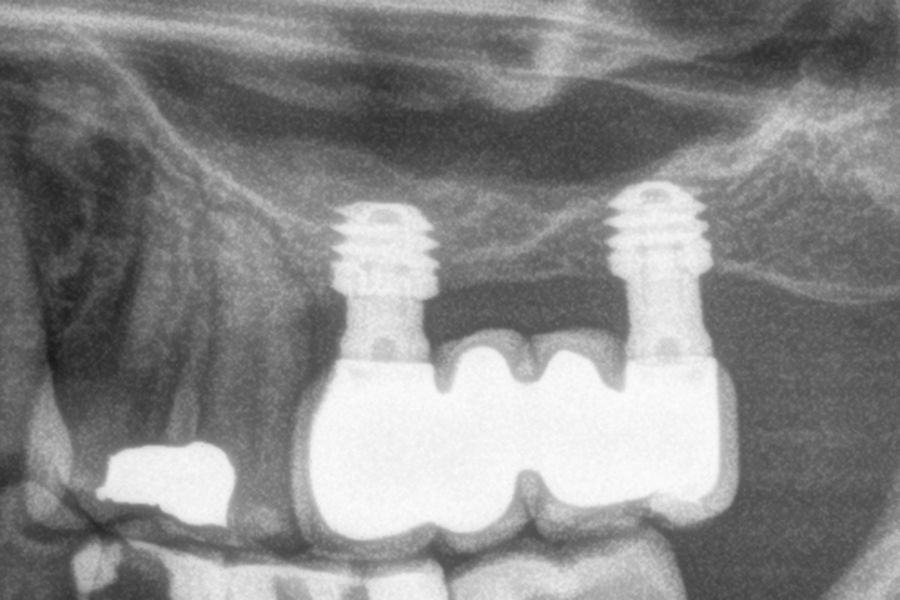

All implants were rehabilitated in two phases and all of them were ferulized to other implants in the rehabilitation. In all cases, screwed prostheses of more than one implant with intermediate elements (transepithelial) were performed, ferulizing to other implants with a length of 4.5 or 5.5 mm. In all situations, a progressive prosthesis load was carried out 6 months after insertion of the implant consisting of a provisional structure finished in resin to move to a definitive metal-ceramic prosthesis. In all cases, the initial transepithelial are preserved to maintain the hermeticity achieved in the first phase of prosthesis manufacture.

Figures 2-19 show one of the cases included in the study.